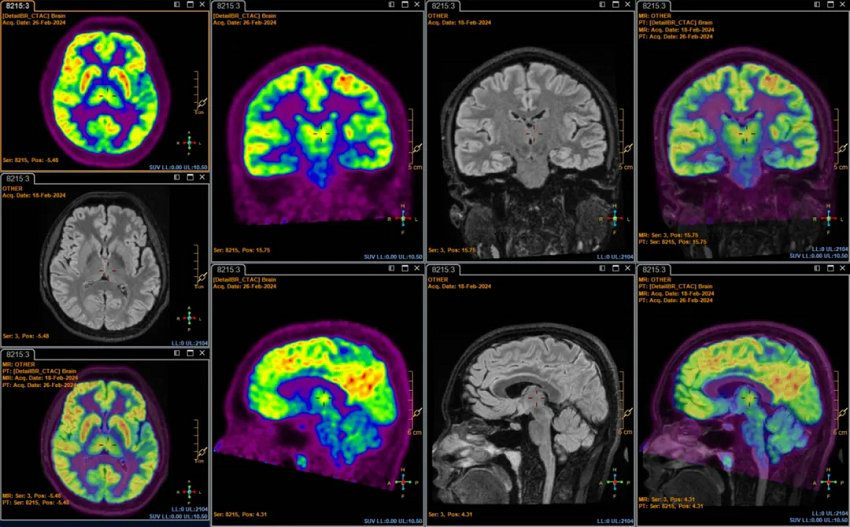

医学影像科医师周丽丹向大家展示了PET在中枢神经系统的应用病例,如PET对神经退行性疾病的诊断价值。尤其是PET与MRI的异机融合,通过医学影像科现有的强大的后处理软件,把异机的MRI图像和PET图像进行完美融合,能够与同机PET-MRI图像相媲美,医院拥有先进的3.0T核磁(MRI),MRI具有较高的分辨率和信噪比,PET与MRI融合从解剖和代谢多维度检出疾病,更好的服务临床。